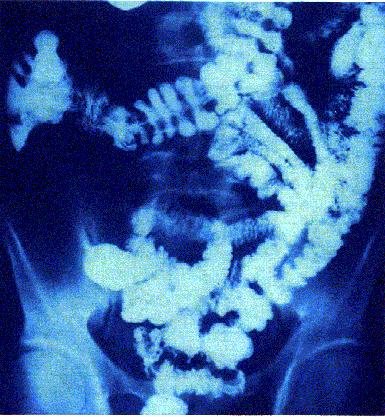

Radiografía de afectación por Crohn